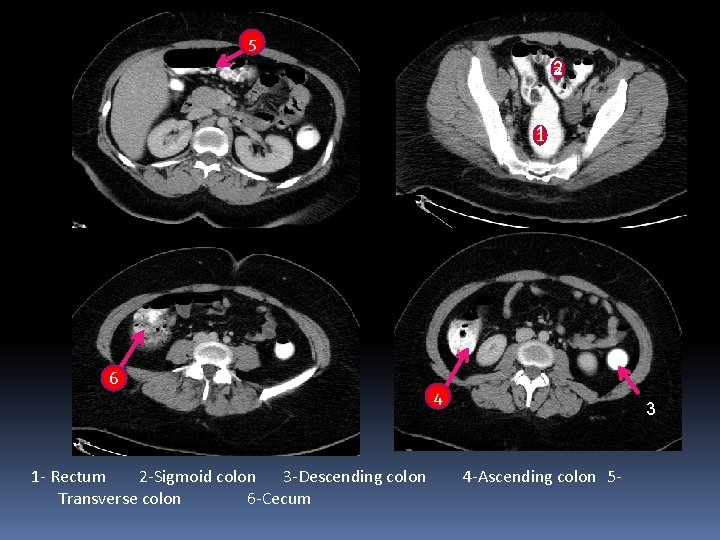

3 2 4 5 6 1

3 2 4 5 1 6 1. 2. 3. 4. 5. 6. Descending colon Splenic flexure Hepatic flexure Ascending colon cecum Sigmoid colon